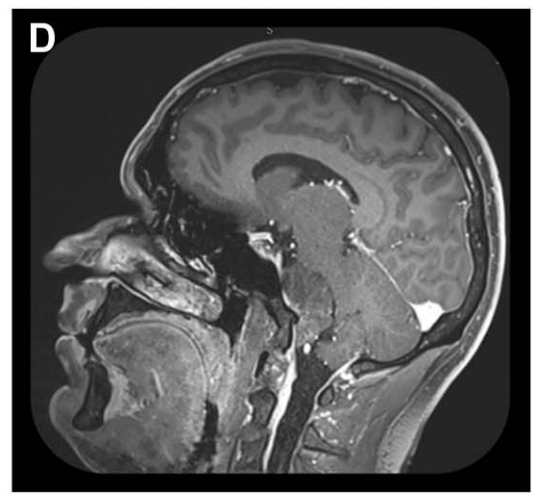

矢状位MRI显示肿瘤经栓塞后血供部分阻断(部分去血管化)